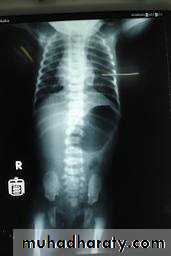

1- Mega ureter2- Retrocaval ureter3- PUJ obstruction 4- Double ureter5- Horse shoe kidney6- Ectopic pelvic kidney Bilateral Hydronephrosis7- Polycystic kidney 8- Copra head 9- Copra head 10- Ectopia vesica